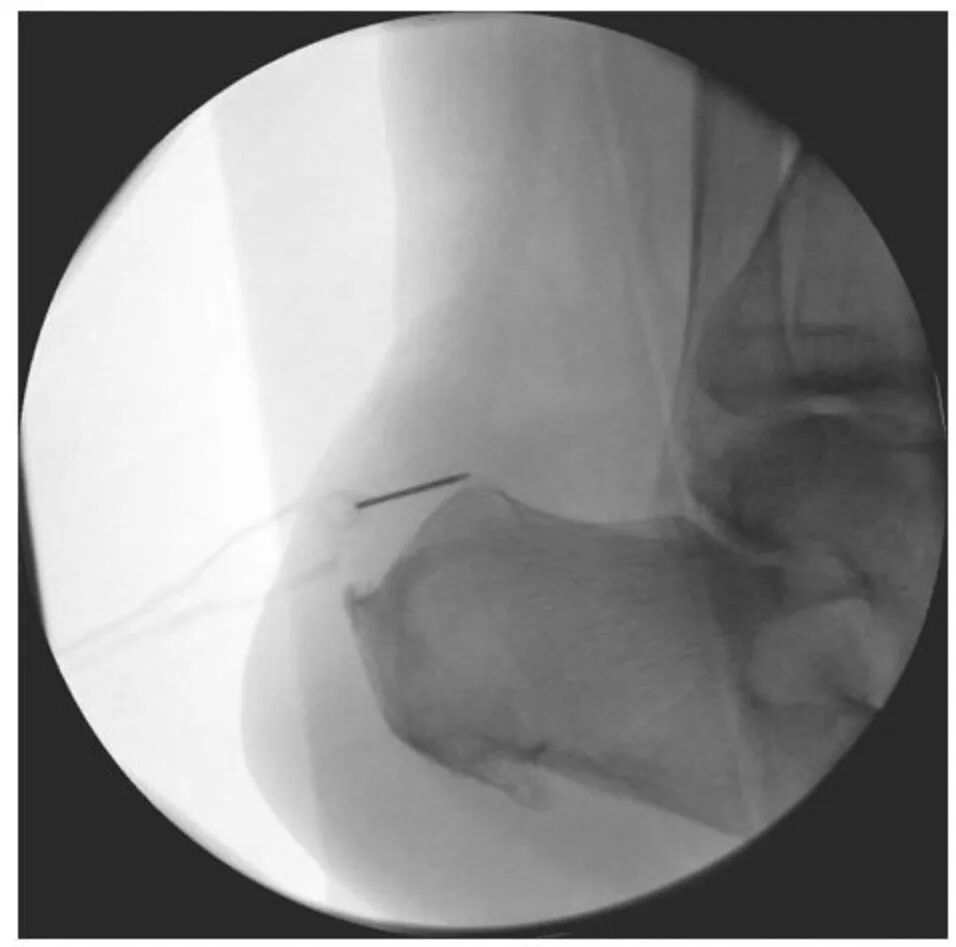

在透视控制下用套管针标记关节镜和切除器械的进入点。此处显示可良好到达Haglund骨赘。

通过C臂机监视切除情况,应显示Haglund畸形被平滑切除。